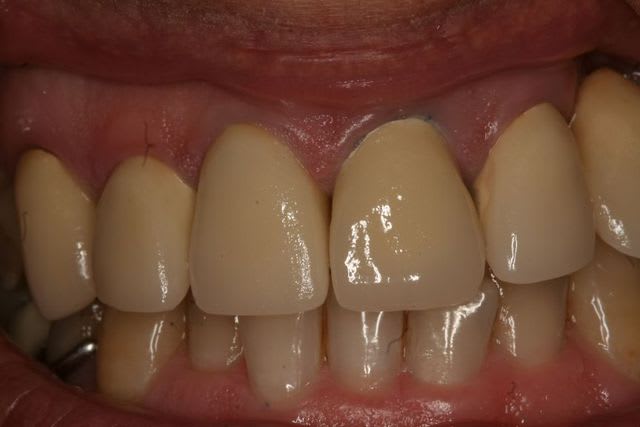

18/04/2011 à 22h22

Après.

Pas de la grande prothèse mais pour un bénéficiaire de la CMU c'est pas mal.

Ce qui a été fait :

Endo/RTE 24

Endo/RTE dents antérieures

Endo/RTE 17 et 47

Montage arc facial articulateur et réalisation de provisoires de labo à DV + 3mm

Taille + adaptation des provisoires

Empreinte pour inlay core

Empreinte inlay core en place et remontage sur articulateur avec arc facial

CC sur 17 et 37

CCM sur 13 12 11 21

Bridge 22 -> 24 (initialement prévu 21, 22 -> 24 mais le labo a eu une déformation, donc je l'ai séparé).

Stellite 5 éléments Md

Le tout pour 4200 € en gros.

Frais de labo :

2 CC = 69.80

7 CCM = 609

Provisoires = 80

Total = 758€

Me reste :

4200 - 1680 - 758 = 1762 € avant charges sociales et IR...

Autant dire que c'est pour s'entrainer...